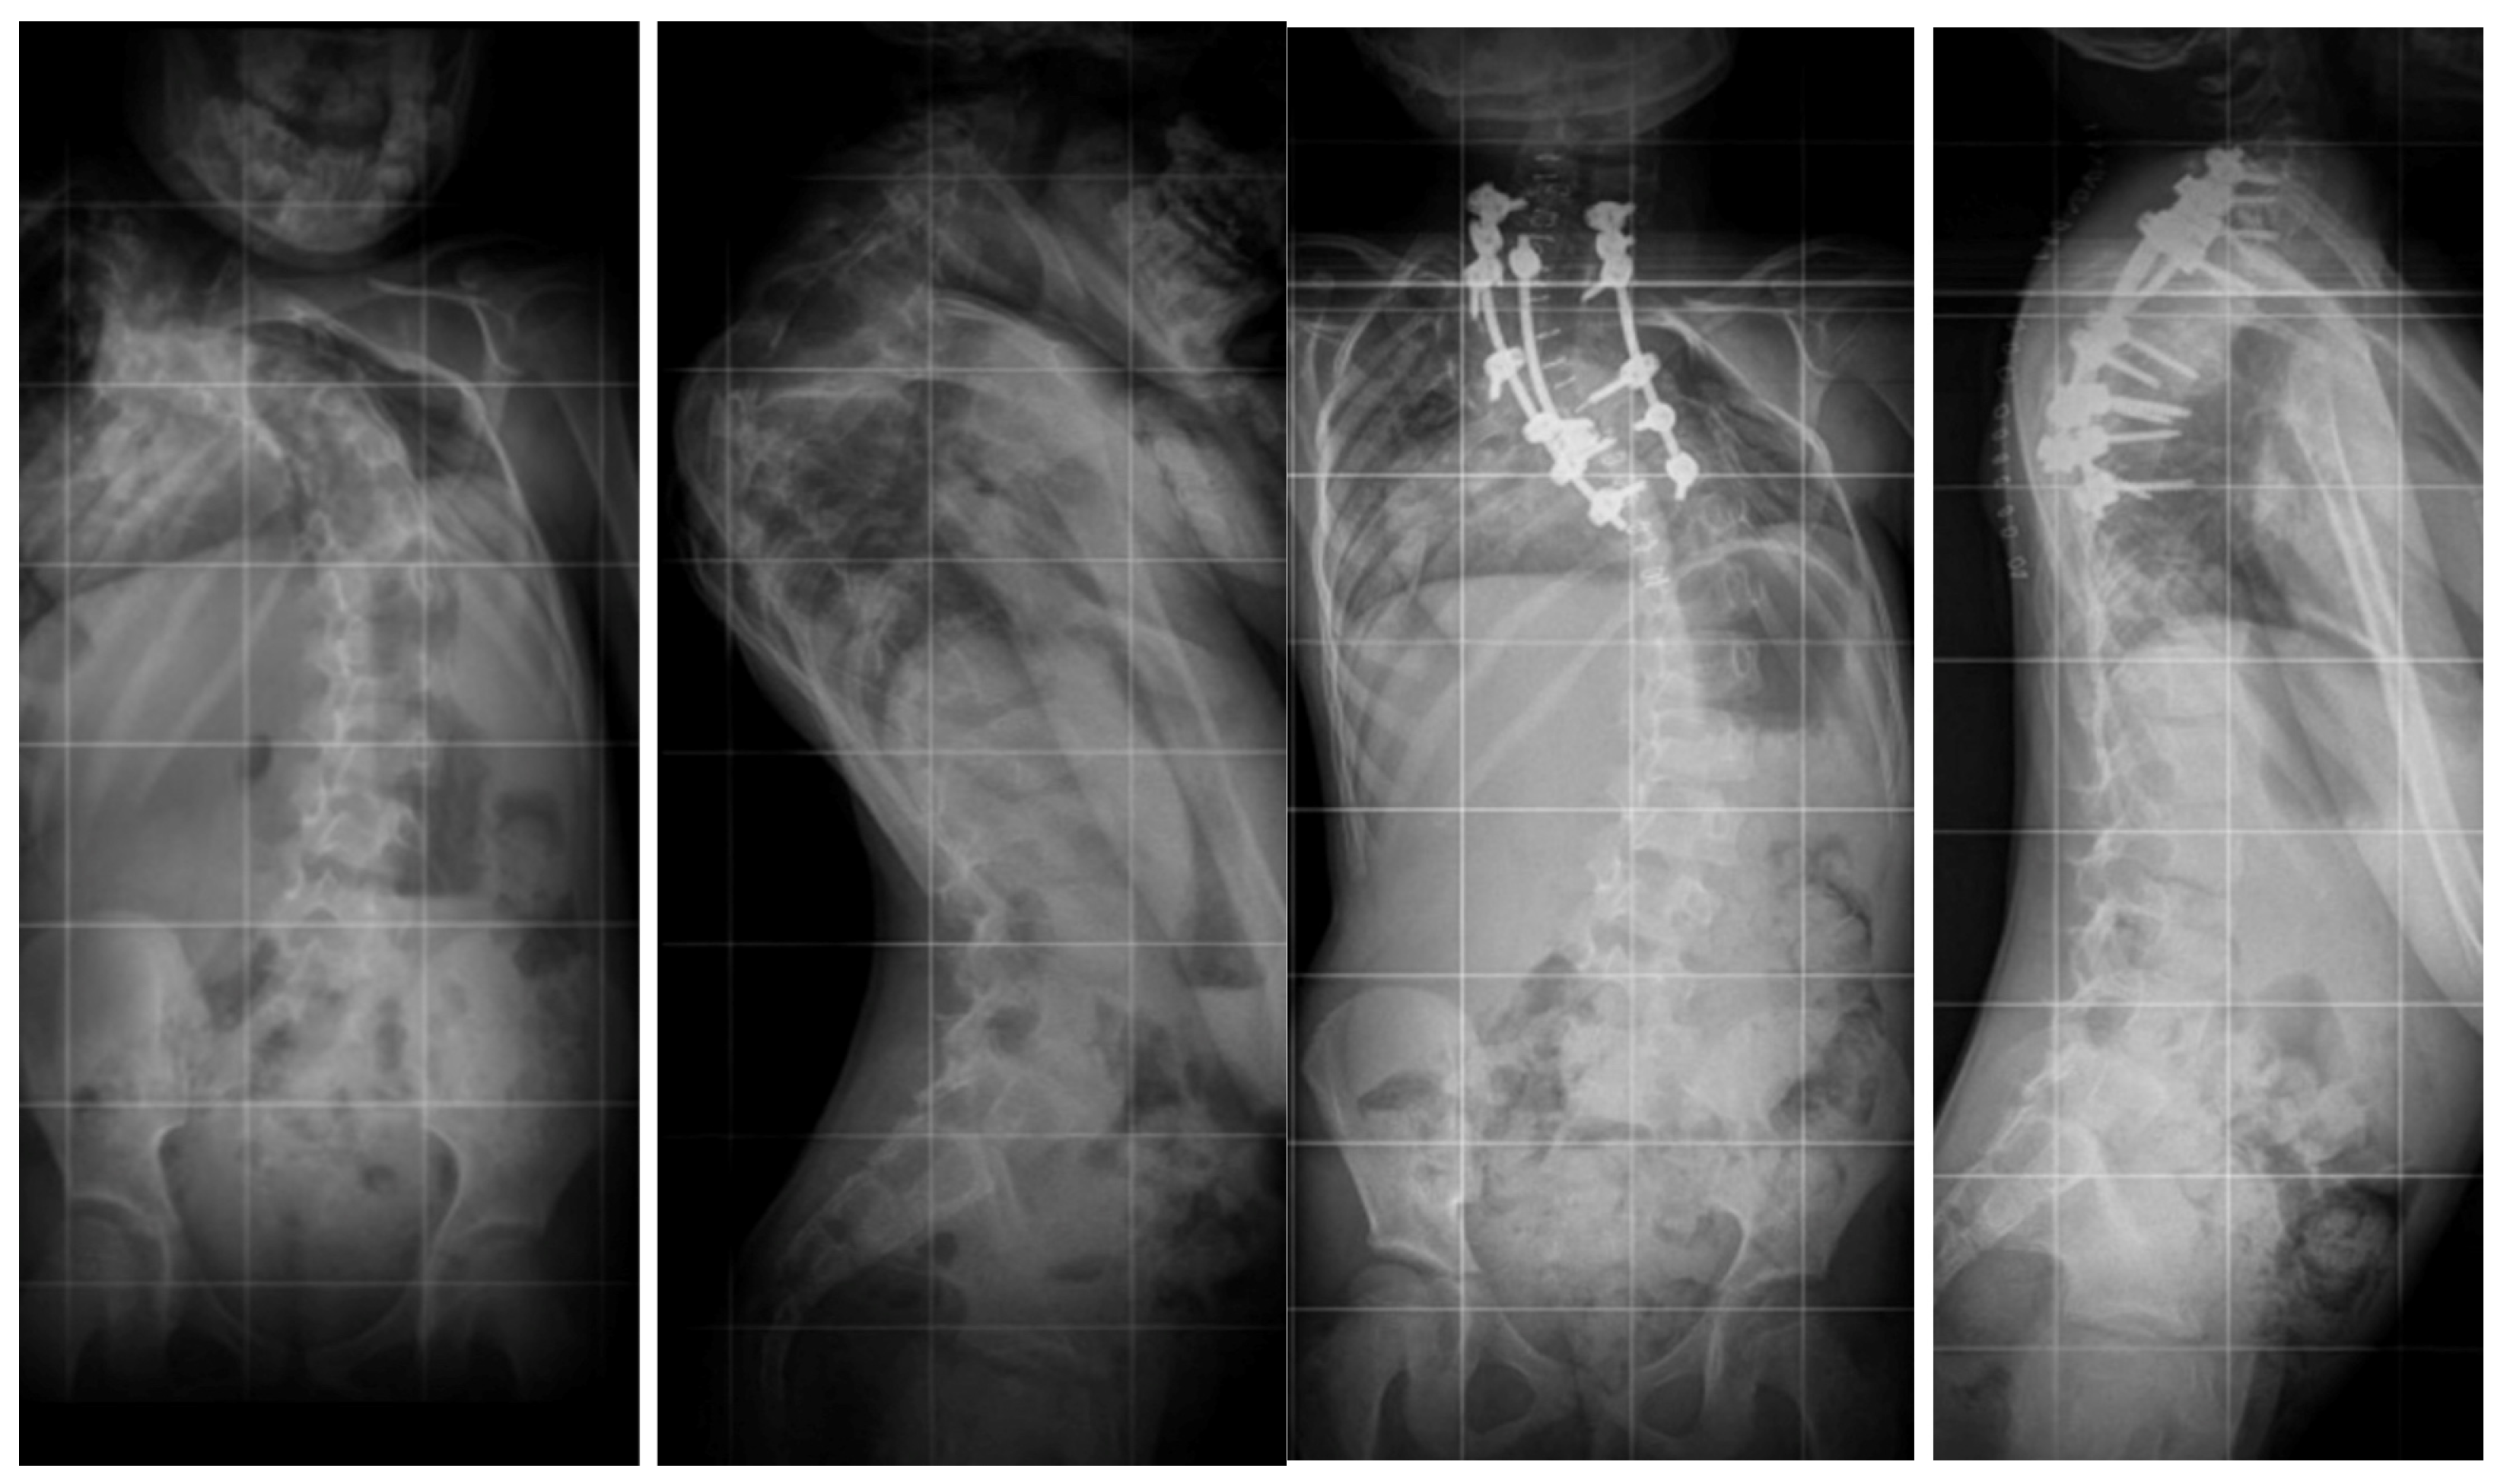

6.1. Radiographic Evaluation

6.2. Advanced Imaging Modalities

7.3. Surgical Techniques

7.3.3. Hemivertebrectomy